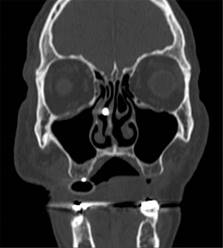

Paciente masculino de 69 años de edad con historia de diabetes mellitus tipo 2 en tratamiento con metformina y clorpropamida, hipertensión arterial en tratamiento con losartán y amlodipino. Se presenta al servicio de urgencias por mostrar cefalea, dolor torácico, tos, mialgias, artralgias y disnea de una semana de evolución. A su ingreso muestra frecuencia cardiaca 114 lpm, frecuencia respiratoria de 24 rpm, saturación de oxígeno de 80% sin apoyo de oxígeno suplementario, glucosa 587 mg/dl, leucocitos de 25,690 cel/mm3, neutrófilos 85%, linfocitos 1.2%, hemoglobina 16.3 g/dl, procalcitonina 3.78 ng/dl, gasometría arterial con pH 7.41, pCO2 21 mmHg, PO2 35 mmHg, HCO3 13 mmol/l, saturación de oxígeno 62%. Se realiza prueba rápida de antígeno para SARS-CoV-2 resultando positiva, tomografía axial computarizada (TAC) de tórax en la que se observan datos radiológicos sugestivos de infección por SARS-CoV-2 (Figura 1), se inicia manejo con oxígeno suplementario, bomba de infusión de insulina, carbapenémicos, antihipertensivos, dexametasona y profilaxis antitrombótica con enoxaparina. A las 48 horas de su ingreso continúa con choque séptico, se inician aminas vasopresoras, se realiza intubación orotraqueal y soporte con ventilación mecánica invasiva, se coloca sonda nasogástrica (SNG), la cual 24 horas posterior a su colocación reporta hematemesis acompañada de distensión abdominal, leucocitosis de 40,000 cel/mm3, se realiza TAC abdominopélvica simple, la cual revela neumatosis gástrica y neumoperitoneo (Figura 2), se efectúa laparotomía exploradora urgente encontrando necrosis de la curvatura mayor del estómago, se lleva a acabo gastrectomía vertical con engrapadora GIA cartuchos morados de 45 y 60 mm (Figura 3), se refuerza línea de grapeo con sutura continua prolene 00, se coloca sonda de yeyunostomía de alimentación a 60 cm del ángulo de Treitz y se dejan drenajes tipo Saratoga. A las 24 horas postoperatorias paciente reporta estabilidad hemodinámica y se suspenden aminas vasopresoras, se inicia nutrición enteral con dieta elemental. El quinto día postquirúrgico muestra adecuada tolerancia a dieta enteral por yeyunostomía, se realiza prueba con azul de metileno por SNG sin evidencia de fugas y descenso de leucocitos a 24,000 cel/mm3. Se recaba resultado de histopatología, el cual revela necrosis panmural asociada a trombosis arterial secundaria a microorganismos compatibles con Mucor sp., por lo que se inicia manejo con anfotericina B (Figuras 4 y 5). En el seguimiento muestra buena evolución, se realiza TAC abdominopélvica con contraste por SNG, la cual descarta fugas y colecciones intraabdominales y se corrobora integridad de la pared gástrica, se retiran drenajes y se da alta de cirugía general el día nueve postquirúrgico continuando manejo a cargo del servicio de medicina interna. Durante los siguientes días de hospitalización, el paciente presenta deterioro cardiovascular y pulmonar, se toma urocultivo, el cual evidencia crecimiento de Candida tropicalis, se realiza TAC de cráneo, tórax y abdominopélvica con contraste oral (Figuras 6 y 7), continúa sin evidencia de fugas a nivel abdominal, se descarta mucormicosis rinocerebral y pulmonar, se reporta probable neumonía bacteriana sobreañadida y neumopatía intersticial secundaria a COVID-19, persiste deterioro clínico y choque refractario, el paciente fallece a 29 días de su ingreso.

Figura 1: Tomografía axial computarizada (TAC) de tórax en la que se observan datos radiológicos sugestivos de infección por SARS-CoV-2.